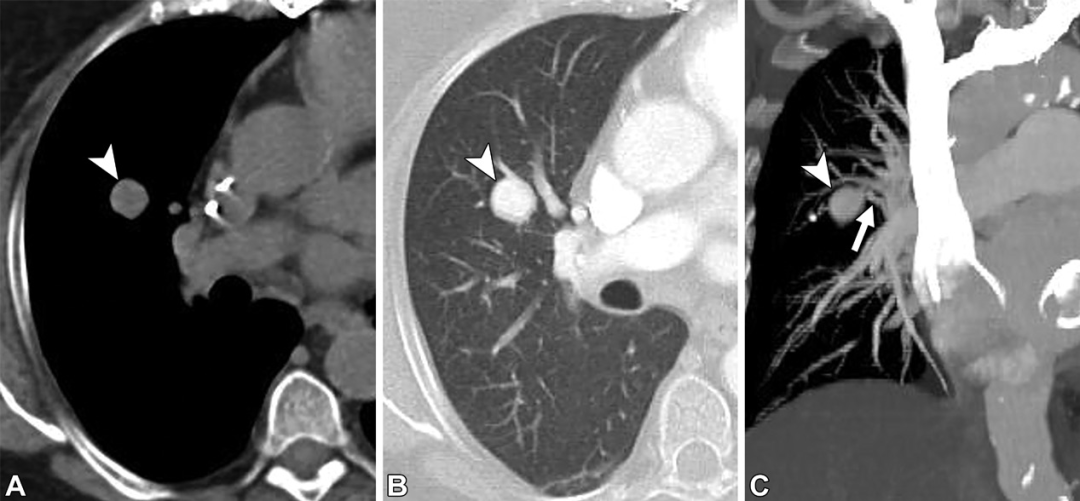

肉芽肿。36岁男性。轴位CT图,可见簇状结节(白色圆圈),中心呈高密度,外周可见小动脉(白色箭头)。以上表现最提示肉芽肿。后续基因检测及头颅磁共振均为阴性,患者也没有遗传性出血性毛细血管扩张症的家族史。

肉芽肿。31岁男性,有遗传性出血性毛细血管扩张症家族史。(A至C)轴位CT增强图,可见左肺下叶病变,伴供血动脉(白色箭头)以及中心高密度(白色星号),未见引流静脉。(D)随诊CT5年后,病变变小(白色星号),开始钙化。提示肉芽肿。